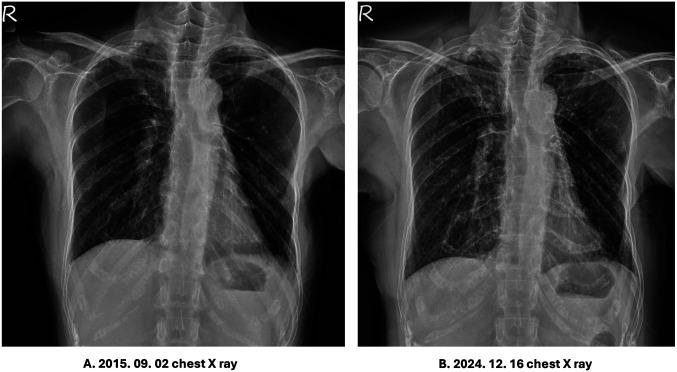

We present the case of a 69-year-old female diagnosed with Sjögren's syndrome, SLE, and ILD. The patient exhibited chronic symptoms, including xerostomia, xerophthalmia, and respiratory distress, for which she had been receiving corticosteroids and immunomodulatory therapy. Given the persistent disease burden and concerns regarding long-term immunosuppressive therapy, molecular hydrogen therapy was introduced as an adjunctive treatment. Over several months, the patient experienced notable clinical improvements, including resolution of xerostomia, insomnia, dyspnea, chest pain, and dizziness. These symptomatic improvements correlated with favorable immunological shifts in T and B cell subsets, enhanced pulmonary imaging findings, and a reduction in inflammatory markers. Additionally, the patient reported a significant decrease in fatigue, allowing corticosteroid tapering and less reliance on nighttime oxygen. Ongoing hydrogen therapy with high-dose vitamin C maintained disease stability and improved quality of life.

我们报告一例69岁女性,诊断为干燥综合征、SLE和ILD。该患者表现出慢性症状,包括口干、眼干和呼吸窘迫,为此她一直在接受皮质类固醇和免疫调节治疗。鉴于持续的疾病负担以及对长期免疫抑制治疗的担忧,引入分子氢疗法作为辅助治疗。在几个月的时间里,患者的临床症状有显著改善,包括口干、失眠、呼吸困难、胸痛和头晕症状的缓解。这些症状的改善与T和B细胞亚群的有利免疫变化、肺部影像学表现的改善以及炎症标志物的减少相关。此外,患者报告疲劳感显著减轻,允许逐渐减少皮质类固醇用量并减少对夜间吸氧的依赖。持续的氢疗法联合高剂量维生素C维持了疾病稳定并改善了生活质量。